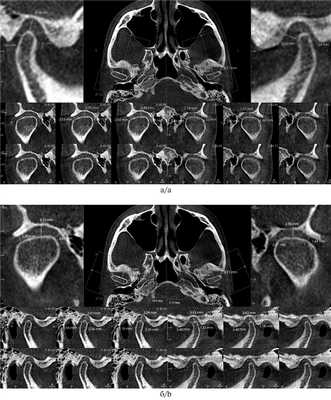

Кроме того, необходимо обращать внимание на симметричность расположения височных ямок при ориентации черепа по срединно-небному шву в корональной проекции, так как если они находятся на разных уровнях, то клинически врач увидит наклон нижней челюсти, что может свидетельствовать о скелетной ротации сфенобазилярного синхондроза — краниальный ROLL (рис. 4).

Рис. 4. Оценка симметричности височных ямок.

Японские ученые K. Ikeda, A. Kawamura и R. в 2011 г. [7] обследовали 22 человек и получили следующие средние размеры суставной щели: 1,3±0,2 мм — переднее суставное пространство, 2,5±0,5 мм — верхнее суставное пространство и 2,1±0,3 мм — заднее суставное пространство. В норме в трансверзальной плоскости медиальный полюс должен располагаться как можно ближе к стенке суставной ямки [8]. Если расстояние между медиальным полюсом и стенкой суставной ямки сильно различается между двумя суставами, это свидетельствует о смещении нижней челюсти в трансверзальном направлении. КЛКТ является отличным инструментом для анализа анатомической структуры суставных головок (рис. 5) [9].

Рис. 5. Ориентиры для измерения суставной щели [7].

а — размеры суставных щелей в кососагиттальном срезе; б — размеры суставных щелей в корональном срезе.